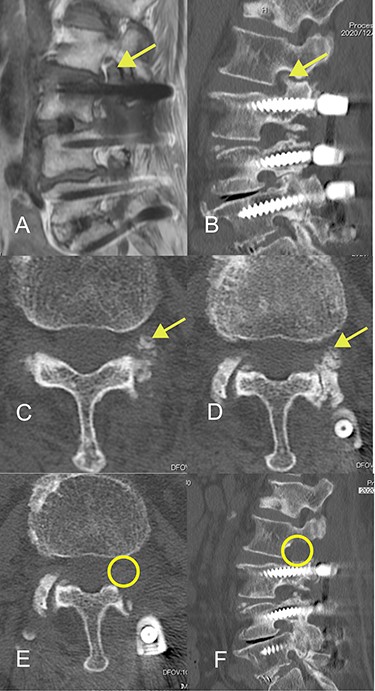

CT images acquired a few months before the onset of radiculopathy had shown a small isolated area of ossification, suggesting that the ossification site had gradually expanded to include the superior articular process over a period of months (Fig. 3).

Progression of ossification of the ligamentum flavum (OLF) on computed tomography (CT) images obtained before onset of radiculopathy. (A) OLF was not found on a CT scan obtained 8 years earlier. (B) A CT image obtained 20 months earlier shows a small isolated area of OLF in the foramen. (C, D) A CT image acquired 4 months earlier shows that the area of OLF had grown slightly and was integrated with the superior articular process. (E, F) A CT image obtained at the time of surgery shows further expansion of OLF.

The changes in CT findings over time in this case (Fig. 3) confirm that the ossification was initially confined to the ligamentum flavum but gradually expanded to the point where it constricted the nerve root at the foramen. However, our review of the literature did not yield any reports of OLF as a cause of radiculopathy at the foramen. Furthermore, although there are some reports on the classification of OLF, most did not include an isolated type. Sato et al. proposed that thoracic OLF be classified as lateral, extended, enlarged, fused or tuberous [14]. Mori et al. subsequently recommended a modified classification system based on whether OLF was small, medium, large, extra-large or central-type [6]. However, Saiki et al. identified four types of OLY, namely, spiny, placoid, nodular and isolated [15]. They also identified that 1% were of an isolated free type, which they defined as a form of ossification that is free in the ligamentum flavum and has no continuity with the articular processes. We consider that our case could be classified as the isolated free type of OLF originally described by Saiki et al. and suspect that this rare type of OLF may have been overlooked in more recent studies, particularly those using CT images. Furthermore, the radiographic and CT images obtained before the onset of radiculopathy in this patient were valuable in that we were able to confirm progression of OLF before the onset of symptoms.